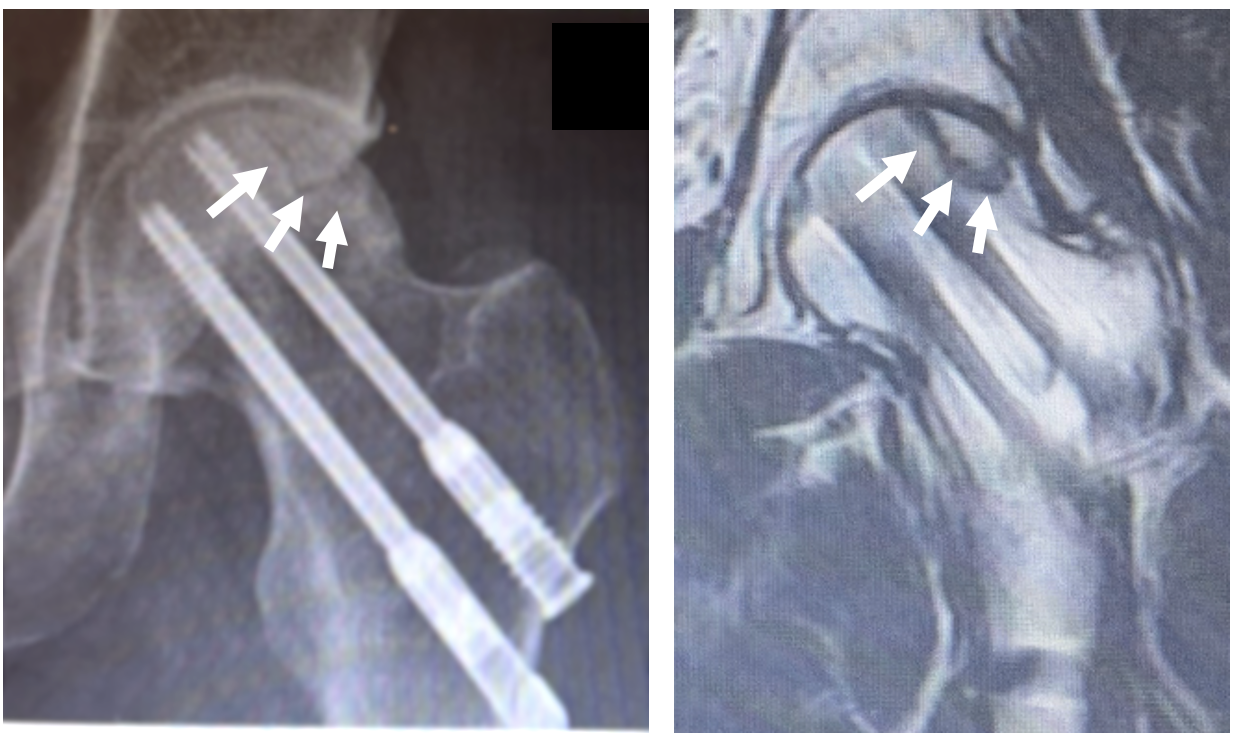

X線画像では骨折の治療の2本のスクリューがあり、その外側の体重がかかる部分にヒビが入ってきていて、MRIでも骨頭壊死と診断

マラソンで転倒され、大腿骨頚部骨折を受傷

近医で骨折手術(スクリュー2本)を施行

骨折手術後5年で左股関節の痛みを生じ、X線、

MRIで骨頭壊死を指摘された。

術前:壊死部のヒビが目立っていた

術後1年:ヒビが徐々に不明瞭  CTでも壊死部の骨再生を確認